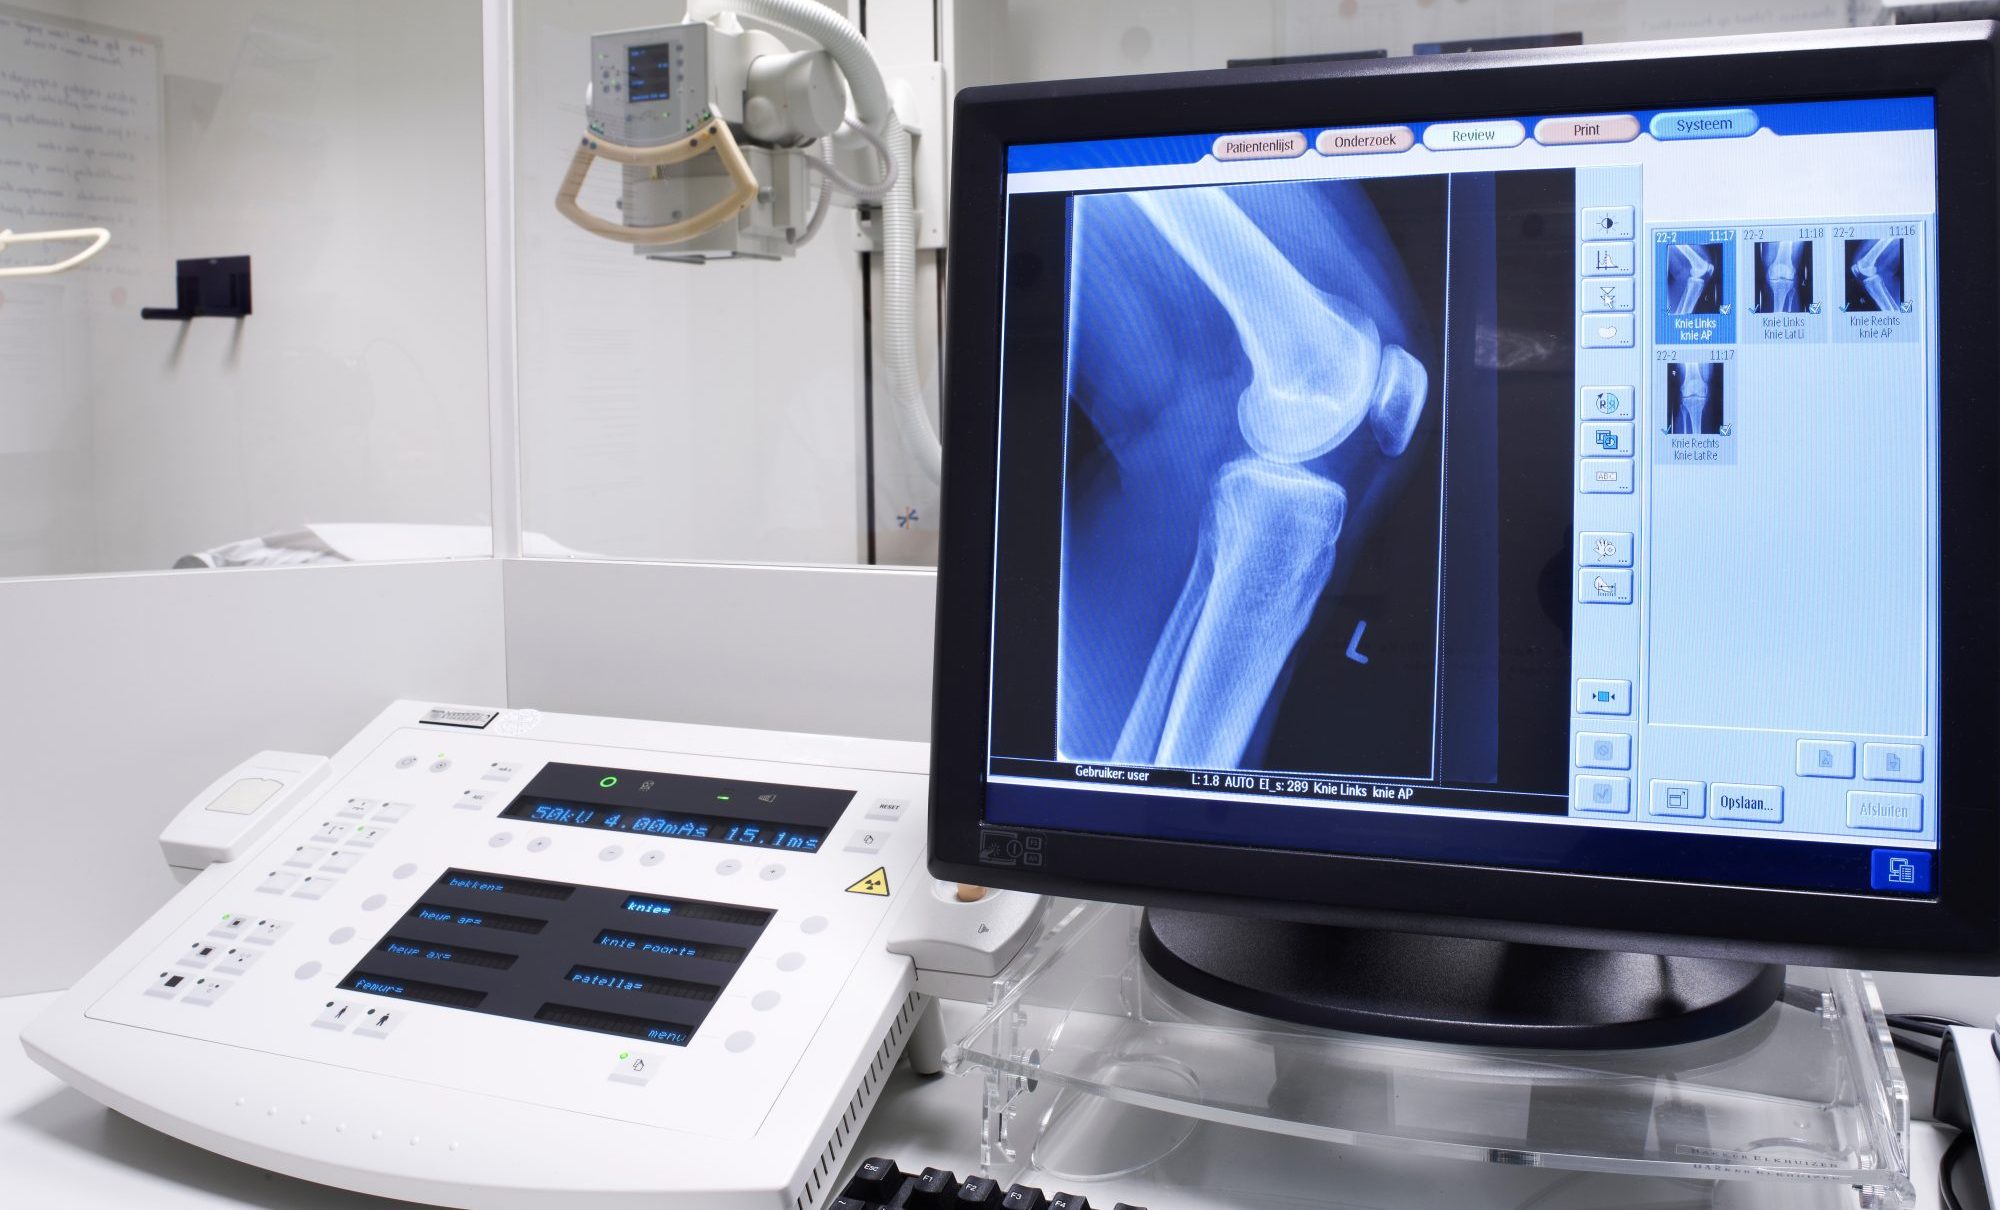

It’s natural to feel confused or even a bit worried if your provider orders an X-ray when you know you don’t have a broken bone. However, X-rays are a versatile diagnostic tool that helps healthcare providers see the whole picture of your health.

While X-rays are famous for showing bones, they can also provide clues about soft tissues and organs. For instance, a chest X-ray is a common diagnostic tool if you have a persistent cough, breathing problems, or chest pain, allowing your provider to look at your lungs and heart. This “internal look” can help your provider differentiate between a simple muscle strain and something that requires medical intervention, like an infection.

An X-ray is more than just a picture of a broken bone; it can be a window into your overall health. If your provider suggests imaging, it is likely because they want to leave no stone unturned as they evaluate your condition and plan your care.